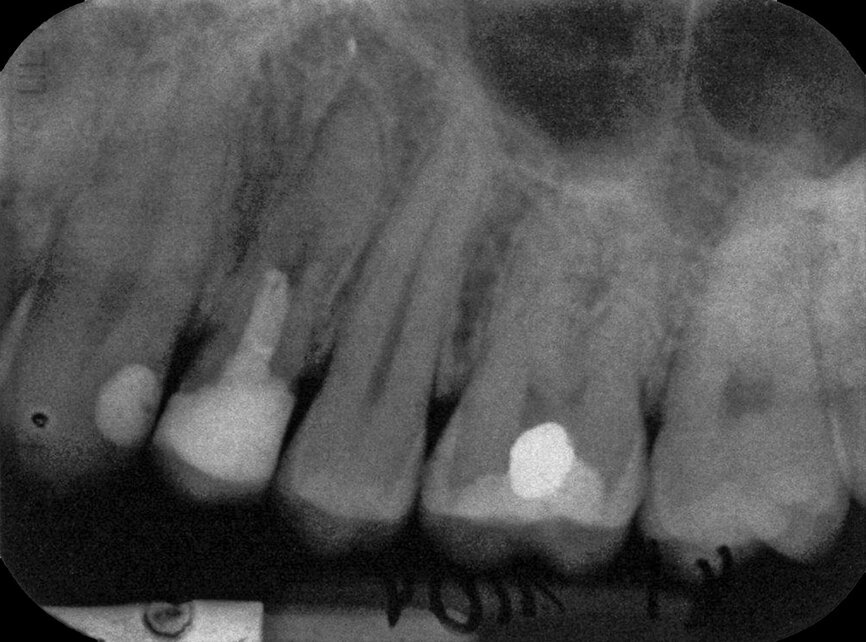

Case 1: Male (born 5 June 1987): Tooth 35

Fig. 3a: 18 March 1997 ante pulpotomy.

Fig. 3b: 18 March 1997 post pulpotomy

Fig. 3c: 6 May 2005 status